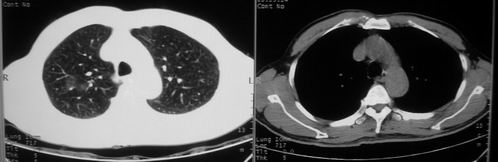

男,62岁,咳血两天。无其他不适。

以炎性肺癌可能性大,建议hrct以删支扩。

片状磨玻璃影,考虑肺泡出血可能性大,其他不排除,建议hrct

考虑肺出血可能性大,建议短期内复查。

病灶呈“磨玻璃影”,较薄,周围无卫星灶,很难一口说是肺结核,建议积极治疗后,短期复查!(支持考虑:肺泡出血!)

右肺上叶可见多发磨玻璃状影,符合肺泡内出血表现,严格意义上讲应该是肺泡内积血。引起出血的原因很多,不一定非得结核所致。